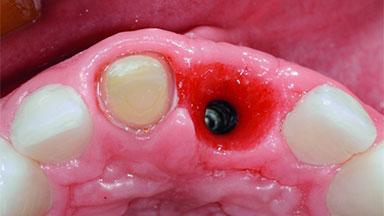

Replacement of an Ankylosed Upper Left Central Incisor: Bone Augmentation and Socket Grafting, Late Placement of an RC Bone Level Implant

A 15-year-old male patient was referred to us by his pediatric dentist in June 2004 for evaluation of treatment options for his failing tooth 21. The patient had recently seen an endodontist for internal bleaching and been advised that there had been significant resorption and ankylosis. The patient’s mother was concerned because the tooth appeared shorter than the adjacent one. His past dental history was significant for trauma (September 2001), where the tooth had been avulsed and reimplanted. Teeth 11 and 21 had been endodontically treated.